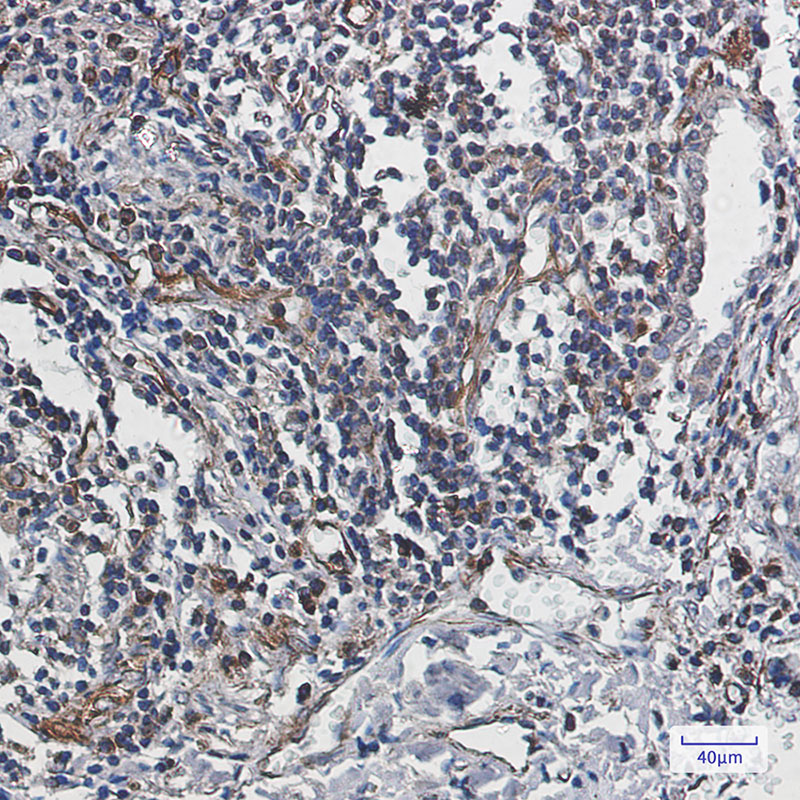

Product Image

| IHC | 1/50-1/100 |